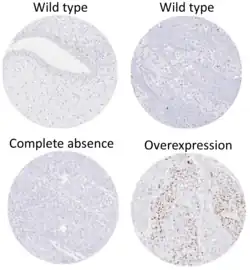

- ^ - Image by Mikael Häggström. Reference: Wojcik, EM; Kurtycz, DFI; Rosenthal, DL (2022). "We'll always have Paris The Paris System for Reporting Urinary Cytology 2022". J Am Soc Cytopathol. 11 (2): 62–66. doi:10.1016/j.jasc.2021.12.003. PMID 35094954. S2CID 246429500.

- ^ Image is taken from following source, with some modification by Mikael Häggström, MD:

- Schallenberg S, Plage H, Hofbauer S, Furlano K, Weinberger S, Bruch PG; et al. (2023). "Altered p53/p16 expression is linked to urothelial carcinoma progression but largely unrelated to prognosis in muscle-invasive tumors". Acta Oncol. 62 (12): 1–10. doi:10.1080/0284186X.2023.2277344. PMID 37938166.{{cite journal}}: CS1 maint: multiple names: authors list (link) - ^ Source for role in distinguishing PUNLMP from low-grade carcinoma:

- Kalantari MR, Ahmadnia H (2007). "P53 overexpression in bladder urothelial neoplasms: new aspect of World Health Organization/International Society of Urological Pathology classification". Urol J. 4 (4): 230–3. PMID 18270948. - ^ Sauter G, Algaba F, Amin MB, Busch C, Cheville J, Gasser T, Grignon D, Hofstaedter F, Lopez-Beltran A, Epstein JI. Noninvasive urothelial neoplasias: WHO classification of noninvasive papillary urothelial tumors. In World Health Organization classification of tumors. Pathology and genetics of tumors of the urinary system and male genital organs. Eble JN, Epstein JI, Sesterhenn I (eds): Lyon, IARCC Press, p. 110, 2004